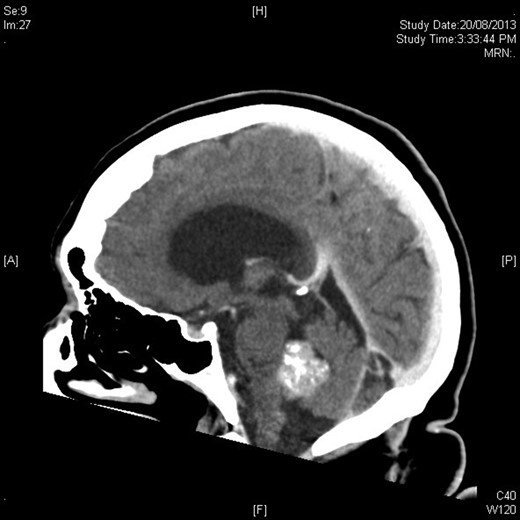

Mrs MM is a 62-year-old female who presented to our institution complaining of a 4-day history of nausea, vomiting and speech difficulties. She initially presented to a peripheral hospital following a fall at home and underwent workup for this. Clinically she scored a Glasgow Coma Scale (GCS) of 14 due to her confusion but had normal strength in all of her limbs. Initial computed tomography brain revealed a 2.6 × 2.5 × 2.1 cm rounded masses enhancing with contrast with areas of calcification in the fourth ventricle and obstructive hydrocephalus (Figs 1 and 2). The following day she underwent magnetic resonance imaging (MRI) brain showed the lesion to be isodense on T1-weighted imaging mildly hypodense on T2-weighted imaging (Fig. 3), and there was no other pathology demonstrated apart from chronic microvascular ischemic changes.

Sagittal figure contrast-enhanced CT brain showing intimate relationship to choroid plexus and associated ventricular dilatation.